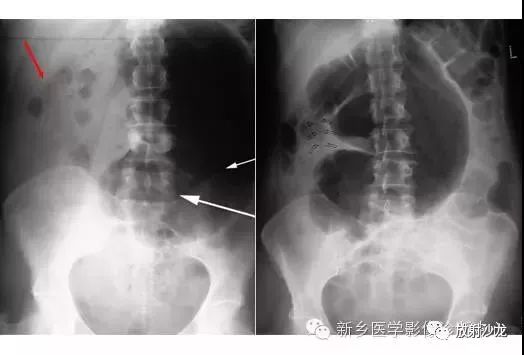

上图腹部平片检查是一6岁男孩,出现呕吐和急性右髂窝疼痛进行的。两个关键的发现在哪里?(提示:通过放射科医生所提供的箭头可以缩小关注点。)

右髂窝多个扩张的小肠襻出现小的钙化结节。小肠袢可与大肠区分开来,因为小肠的环状襞延伸至整个肠壁,而结肠袋只是部分延伸存在。在右下腹(箭头)的钙化结节高度提示阑尾粘连。这个病人开腹手术发现阑尾粘连致小肠梗阻。

腹痛患者的腹部X光片水平位(左侧)和直立位(右侧)所上图示。是什么原因导致该病人的不适呢?

X线片表现出充满整个腹部的乙状结肠扭转。乙状结肠的两端可以理解成一个倒置的朝向骨盆的U型(图U)。在X光片直立位,可以看出气液平面(箭头)。咖啡豆的标志是乙状结肠扭转的典型的表现。充满气体的肠道包绕重叠水肿的肠壁所形成致密的白线,类似于一个咖啡豆。在这些X光片中,大肠的其余部分均不膨大,大概是因为扭转的点不造成阻塞,从而使消化产物可进入乙状结肠。